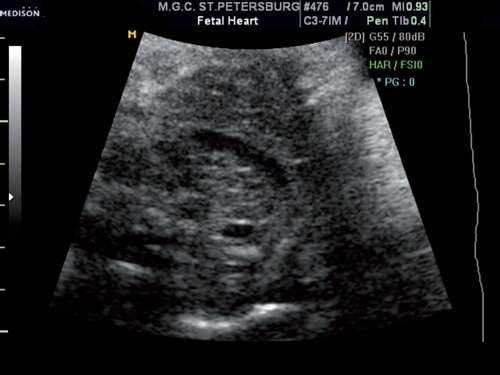

Выше среза через три сосуда в передней трети грудной клетки визуализировался сосуд, размеры которого были сопоставимы с размерами верхней полой вены (рис. 2).

Рис. 2. Поперечное сечение грудной клетки плода выше уровня трех сосудов. Обращает на себя внимание крупный сосуд, располагающийся в передней трети грудной клетки.